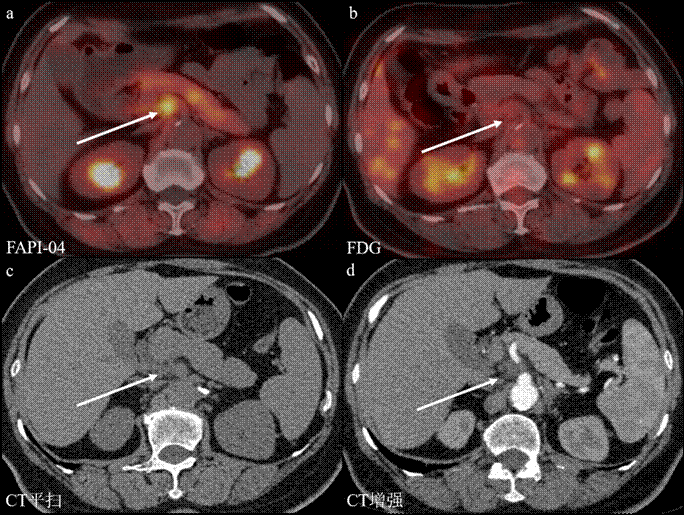

图2:不同检查方法显示转移性淋巴结。a. FAPI PET/CT显像:病灶呈高摄取,可明确诊断;b. FDG PET/CT显像:病灶未见明显摄取,难以诊断;c. CT平扫:病灶呈等密度影,难以诊断;d. CT增强:病灶未见明确强化,难以诊断。